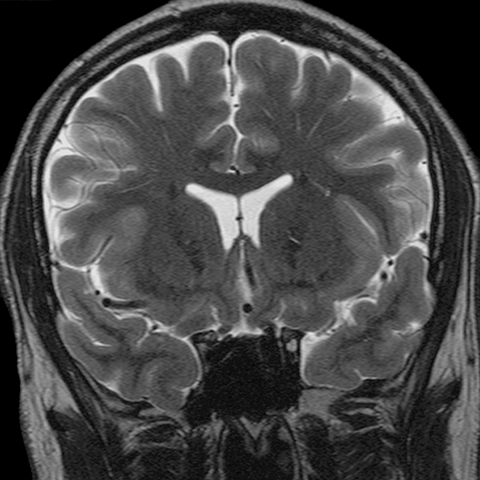

Cranial Meninges (normal) [3 of 8]